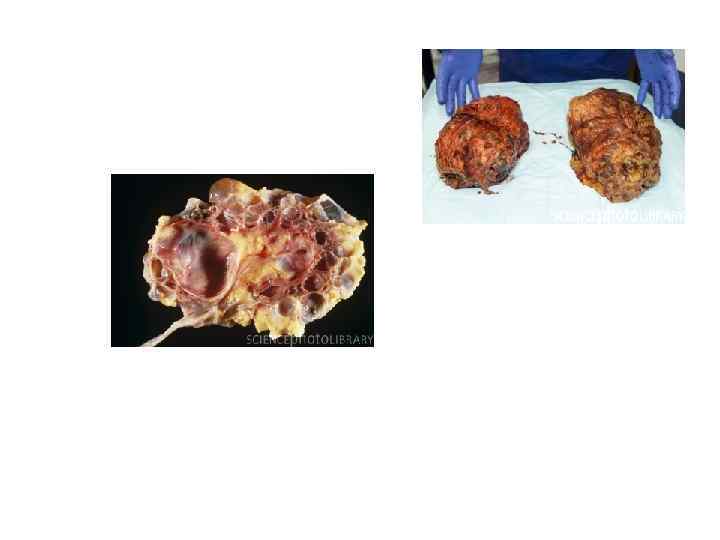

«Хроническая болезнь почек» может быть и обобщающим термином и самостоятельным диагнозом. Несмотря на многообразие этиологических факторов, большинство хронических заболеваний почек имеют единый механизм прогрессирования, а морфологические изменения в почках при почечной недостаточности однотипны и сводятся к преобладанию фибропластических процессов с замещением функционирующих нефронов соединительной тканью и сморщиванию почек.

«Хроническая болезнь почек» может быть и обобщающим термином и самостоятельным диагнозом. Несмотря на многообразие этиологических факторов, большинство хронических заболеваний почек имеют единый механизм прогрессирования, а морфологические изменения в почках при почечной недостаточности однотипны и сводятся к преобладанию фибропластических процессов с замещением функционирующих нефронов соединительной тканью и сморщиванию почек.